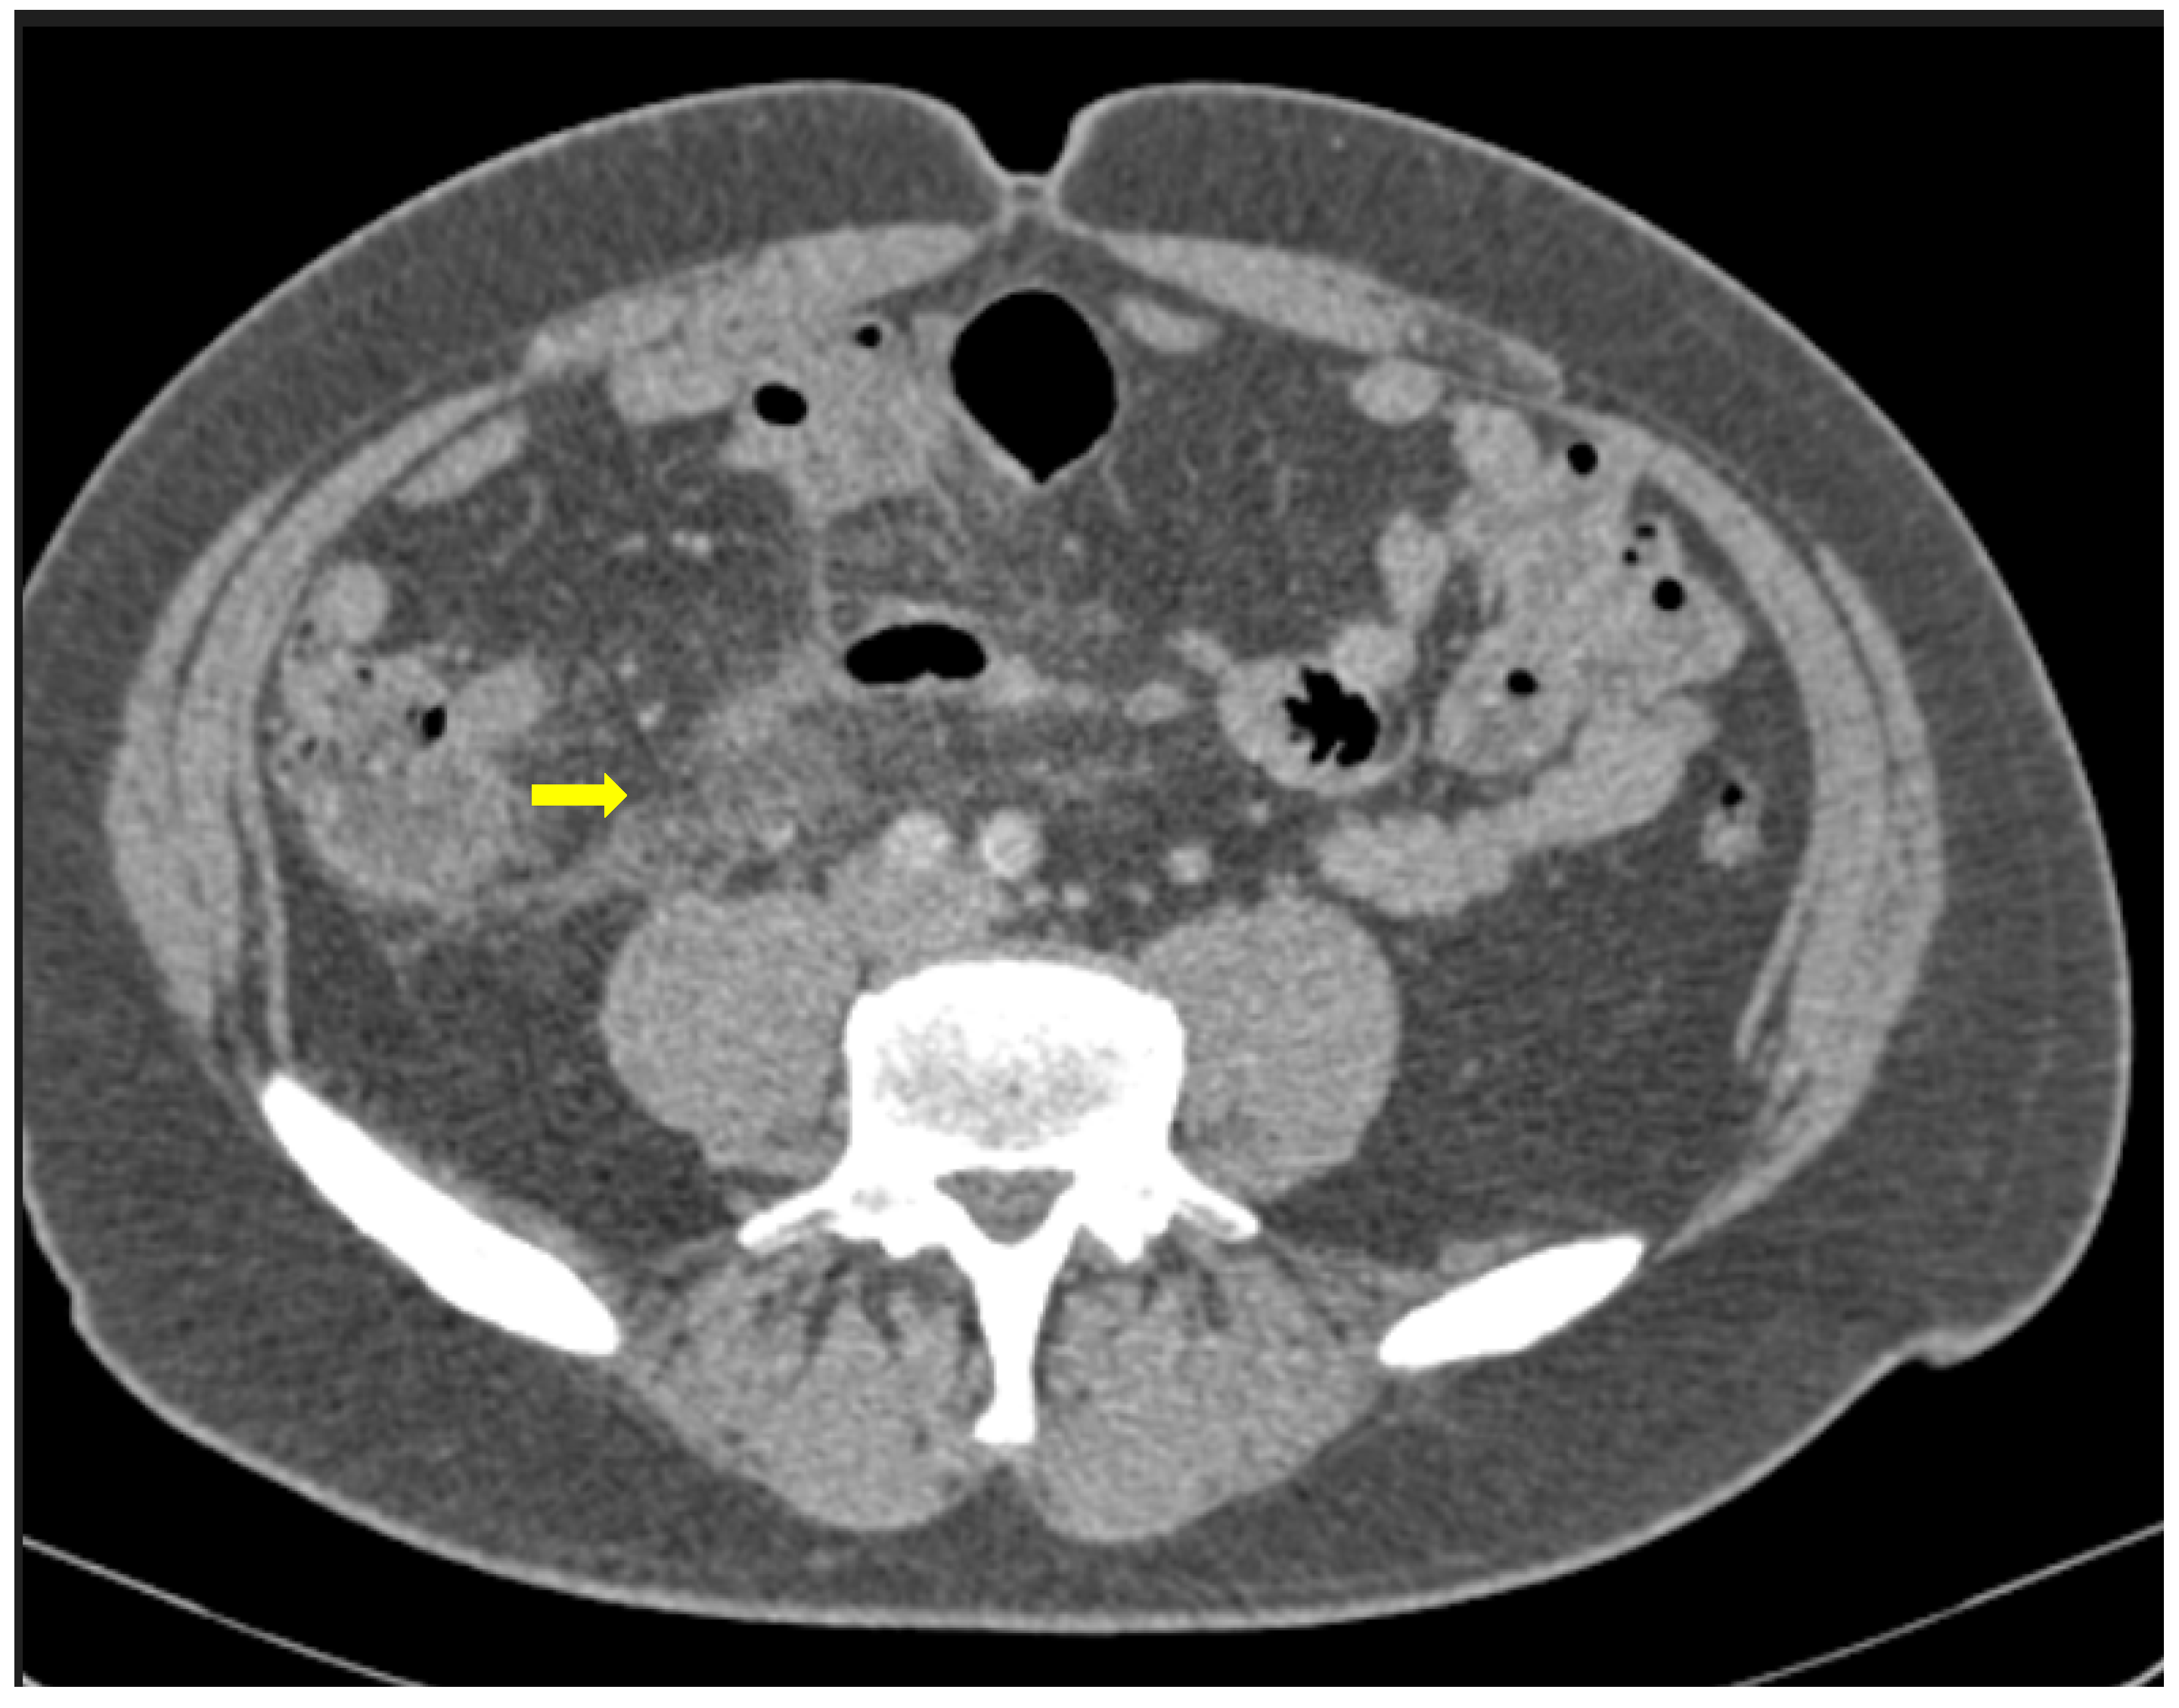

2.6. Bleeding Manifestations

GI hemorrhage is less commonly encountered in abdominal imaging, and CT findings include active intraluminal extravasation of contrast and indirect signs such as luminal distention with blood clots (Figure 11) [56].

Imaging is additionally significant to the treatment plan by identifying the exact site and extent of the bleeding as well as offering a precise and minimally invasive treatment option. Digital Subtraction Angiography can confirm the active bleeding seen as a “contrast blush”, detect the responsible branch and provide occlusion via selective embolization.

Figure 11. A 75-year-old intubated patient with COVID-19 presented with hematemesis, hypotension and acute drop of hemoglobin level. Computed Tomography revealed active intraluminal extravasation of contrast into the 2nd part of duodenum (arrow) on arterial phase (a). Further pooling of the contrast (arrowhead) is shown on portal phase (b).